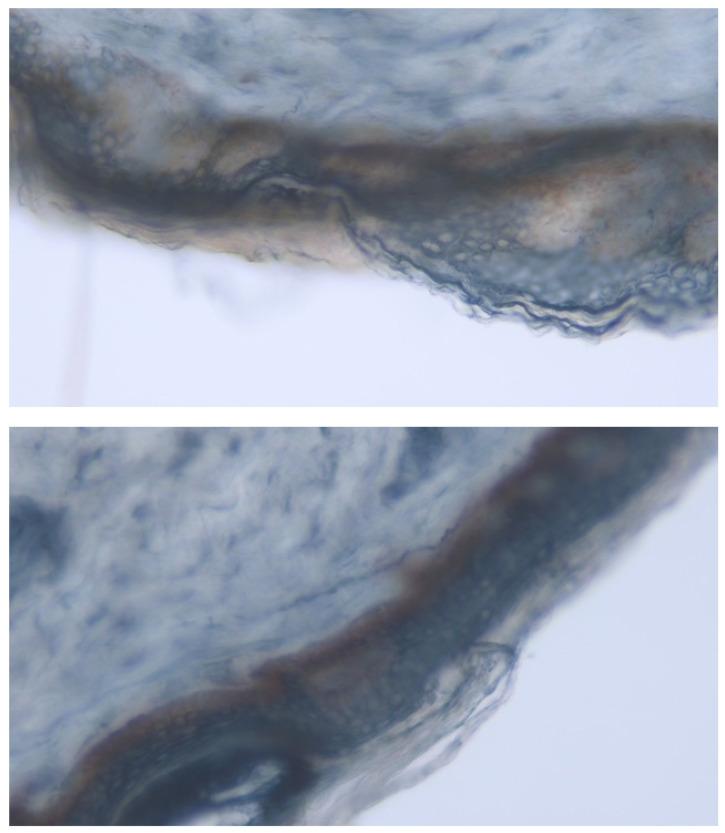

The aim of this study was to evaluate the effects of spinal cord stimulation (SCS) on pain, neuropathic symptoms, and other health-related metrics in patients with chronic painful peripheral neuropathy (PN) from multiple etiologies. A prospective single center observational longitudinal cohort study assessed SCS efficacy from April 2023 to May 2024, with follow-ups at 2, 4, 6, and 12 months in 19 patients suffering from the painful polyneuropathy of diverse etiologies: diabetic (DPN), idiopathic (CIAP), chemotherapy-induced (CIPN), and others. Patients were implanted with a neurostimulator (WaveWriter Alpha, Boston Scientific Corporation, Valencia, CA, USA) and percutaneous leads targeting the lower limbs (T10-T11) and, if necessary, the upper limbs (C4-C7). Stimulation programming was individualized based on patient preference and best response. Assessments were performed before and after implantation and included pain intensity (VAS and DN4), neuropathic pain symptoms (NPSI and SF-MPQ-2), autonomic symptoms (SFN-SIQ and SAS), sensory and small fiber nerve injury (UENS), functionality (GAF), sleep (CPSI), global impression of change (CGI and PGI), and quality of life (EQ-VAS and EQ-5D). Intra-epidermal nerve fiber density (IENFD) via skin biopsy was also performed at baseline (diagnostic) and after 12 months to assess potential small fiber re-growth. Statistical analyses were conducted to determine the evolution of treatment success. To date, 19 patients have undergone implantation and completed follow-up. SCS produced a significant consistent and sustained improvement in pain intensity by 49% in DN4 and 76% in VAS, in neuropathic pain symptoms by 73%, in autonomic symptoms by 26-30%, in the sensorimotor physical exam by 8%, in functionality by 44%, in sleep by 74%, and in quality of life (69% for EQ-VAS and 134% EQ-5D). Both clinicians and patients had a meaningful global impression of change, at 1.1 and 1.3, respectively. Distal intra-epidermal nerve fiber density improved by 22% at 12 months while proximal intra-epidermal nerve fiber density decreased by 18%. SCS is an effective therapy for managing various types of PN.

本研究的目的是评估脊髓刺激(SCS)对多种病因引起的慢性疼痛性周围神经病变(PN)患者的疼痛、神经病变症状及其他健康相关指标的影响。一项前瞻性单中心观察性纵向队列研究于2023年4月至2024年5月评估了SCS的疗效,对19例患有不同病因所致疼痛性多发性神经病变的患者进行了2个月、4个月、6个月和12个月的随访,病因包括糖尿病性(DPN)、特发性(CIAP)、化疗诱导性(CIPN)等。患者植入了神经刺激器(WaveWriter Alpha,美国波士顿科学公司,加利福尼亚州瓦伦西亚),经皮导线靶向下肢(T10 - T11),必要时靶向上肢(C4 - C7)。刺激程序根据患者偏好和最佳反应进行个体化设置。在植入前后进行评估,包括疼痛强度(VAS和DN4)、神经性疼痛症状(NPSI和SF - MPQ - 2)、自主神经症状(SFN - SIQ和SAS)、感觉和小纤维神经损伤(UENS)、功能(GAF)、睡眠(CPSI)、总体变化印象(CGI和PGI)以及生活质量(EQ - VAS和EQ - 5D)。在基线(诊断时)和12个月后还通过皮肤活检进行了表皮内神经纤维密度(IENFD)检测,以评估潜在的小纤维再生情况。进行统计分析以确定治疗成功的进展情况。迄今为止,19例患者已接受植入并完成随访。SCS使疼痛强度显著、持续改善,DN4改善49%,VAS改善76%;神经性疼痛症状改善73%;自主神经症状改善26% - 30%;感觉运动体格检查改善8%;功能改善44%;睡眠改善74%;生活质量改善(EQ - VAS改善69%,EQ - 5D改善134%)。临床医生和患者对总体变化的印象分别为1.1和1.3,均具有意义。12个月时,远端表皮内神经纤维密度提高了22%,而近端表皮内神经纤维密度下降了18%。SCS是治疗各种类型PN的有效疗法。